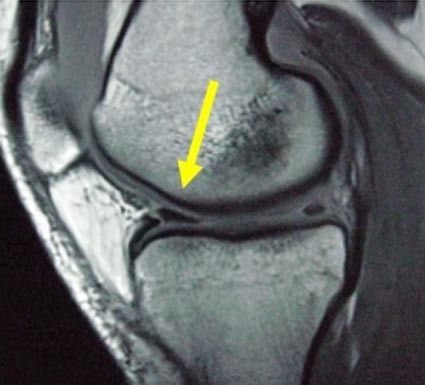

膝関節の骨表面は薄い軟骨で覆われ、大腿骨と脛骨の間に半月というドーナツを半分にしたような板状の軟骨組織が内側と外側に挟まっています。激しい運動などで強く膝を捻ると半月に亀裂が入ることがあります。初期は2~3週ほどで痛みは改善し歩行程度は可...